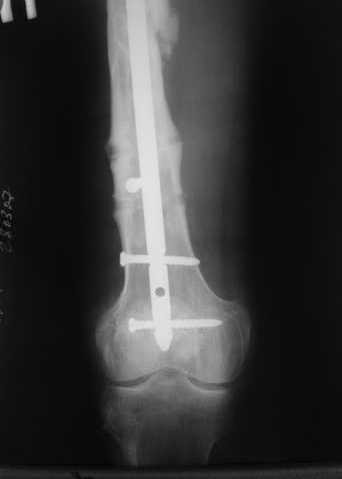

27 марта выполнено удаление блокирующих винтов (сломанный винт пришлось высверливать цапфен-бором), сломанного штифта (дистальный фрагмент удален через канал, образованный разверткой из коленного сустава - image 4),

рассверливание костно-мозгового канала, реостеосинтез штифтом UFN (при проведении штифта в дистальном отломке мы использовали поляризующий винт, диаметр штифта 10 мм). После операции в связи гемартрозом дважды (на 1 и 3 сутки) выполняли пункцию коленного сустава. Сейчас признаков скопления жидкости в полости сустава нет. Послеоперационные рентгенограммы - images 5, 6, 7.

Все здорово! Но, 1)- почему штифт 10мм, а не больше?, 2) - проксимальное блокирование одним вмнтом в статическом положении?

1) Мы располагали штифтом только данного диаметра.

2) По-поводу проксимлаьного блокирующего винта. Винт стоит на 3-5 мм выше нижнего

края динамического отверстия. Препятствий для компрессии отломков пока нет.